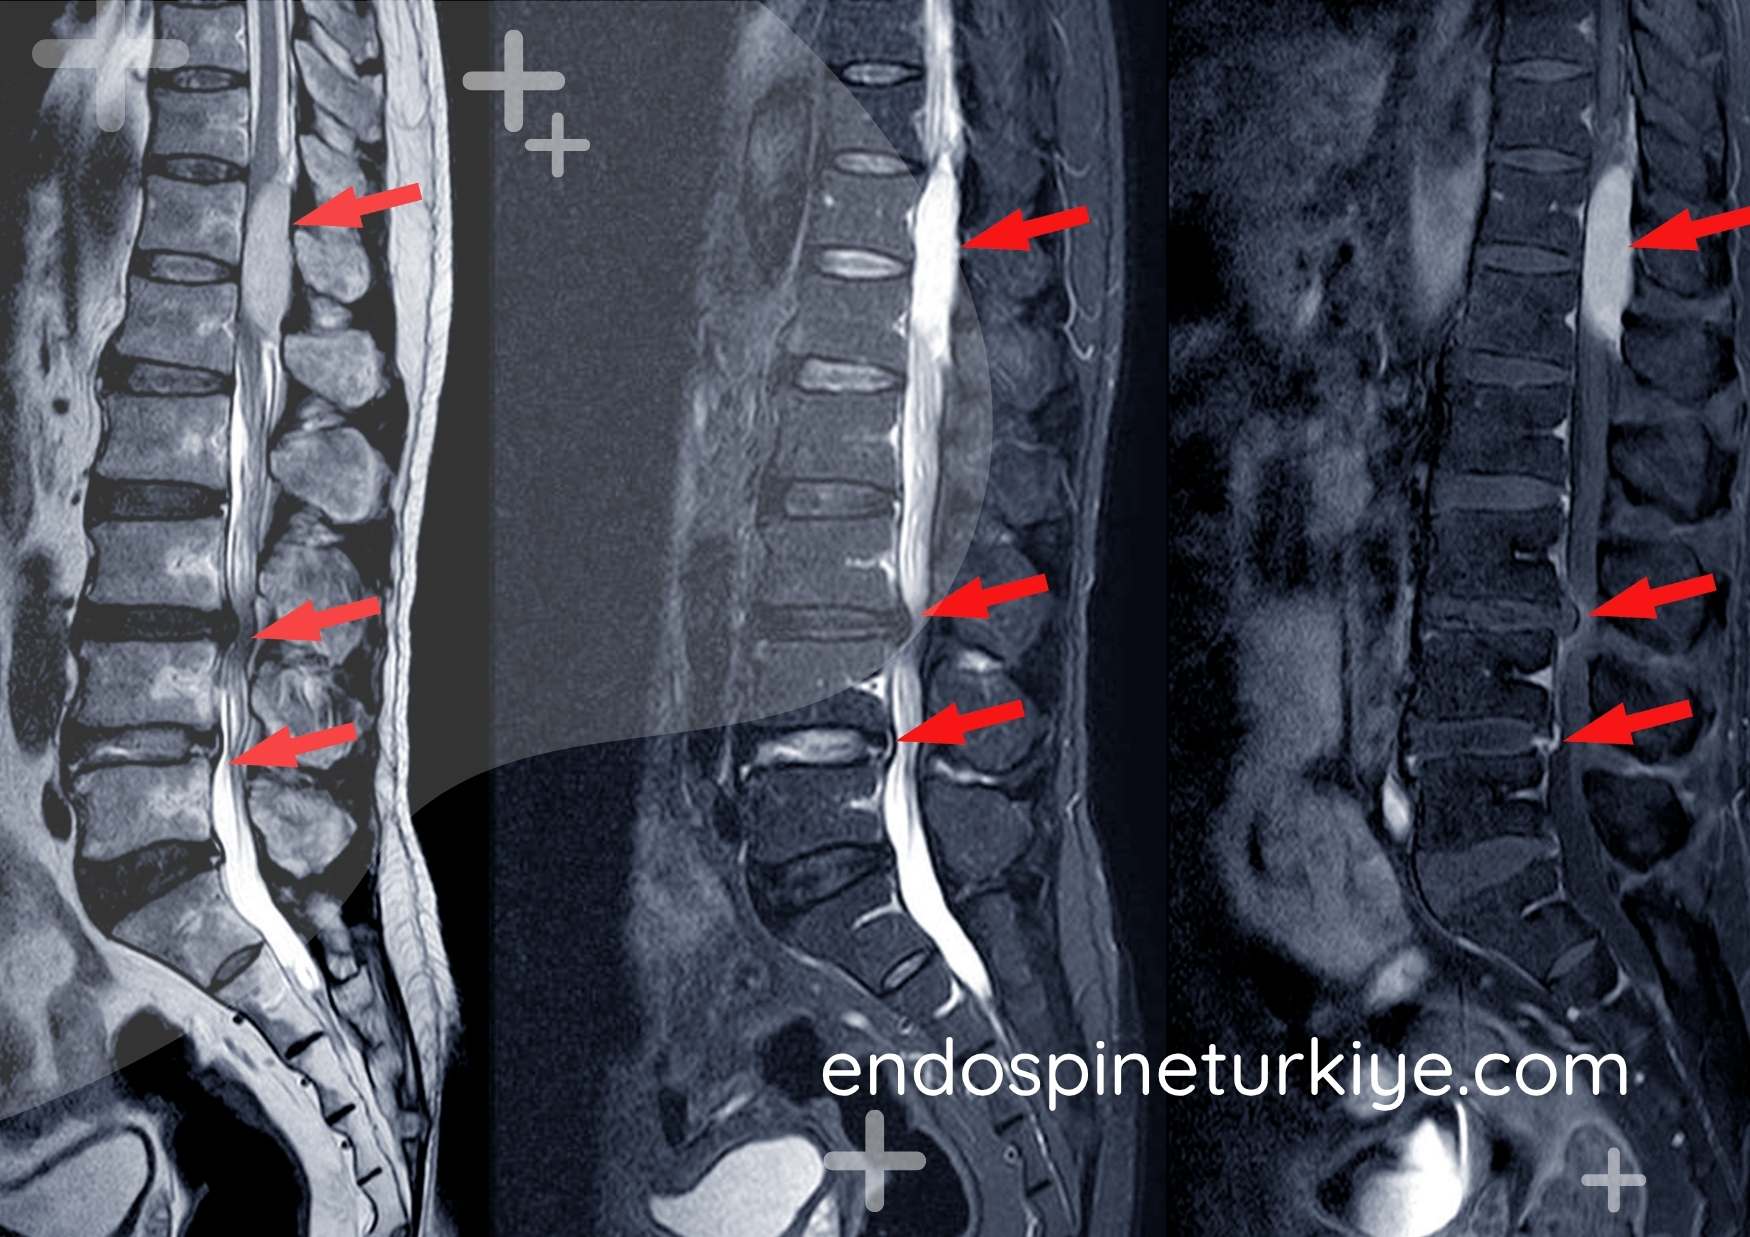

Tam kapalı dar kanal ameliyatı öncesi lomber MR - kanal darlığı teşhisi

Lomber MR görüntüsü - omurga kanalında daralma (spinal stenoz)

Tam kapalı dar kanal ameliyatı öncesi MR - kanal darlığı görüntüsü Ameliyat Öncesi

Tam kapalı endoskopik dar kanal ameliyatı sonrası MR - dekompresyon sonucu Ameliyat Sonrası